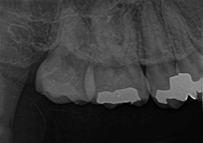

レントゲンでのむし歯のチェックや噛み合わせなどのチェック